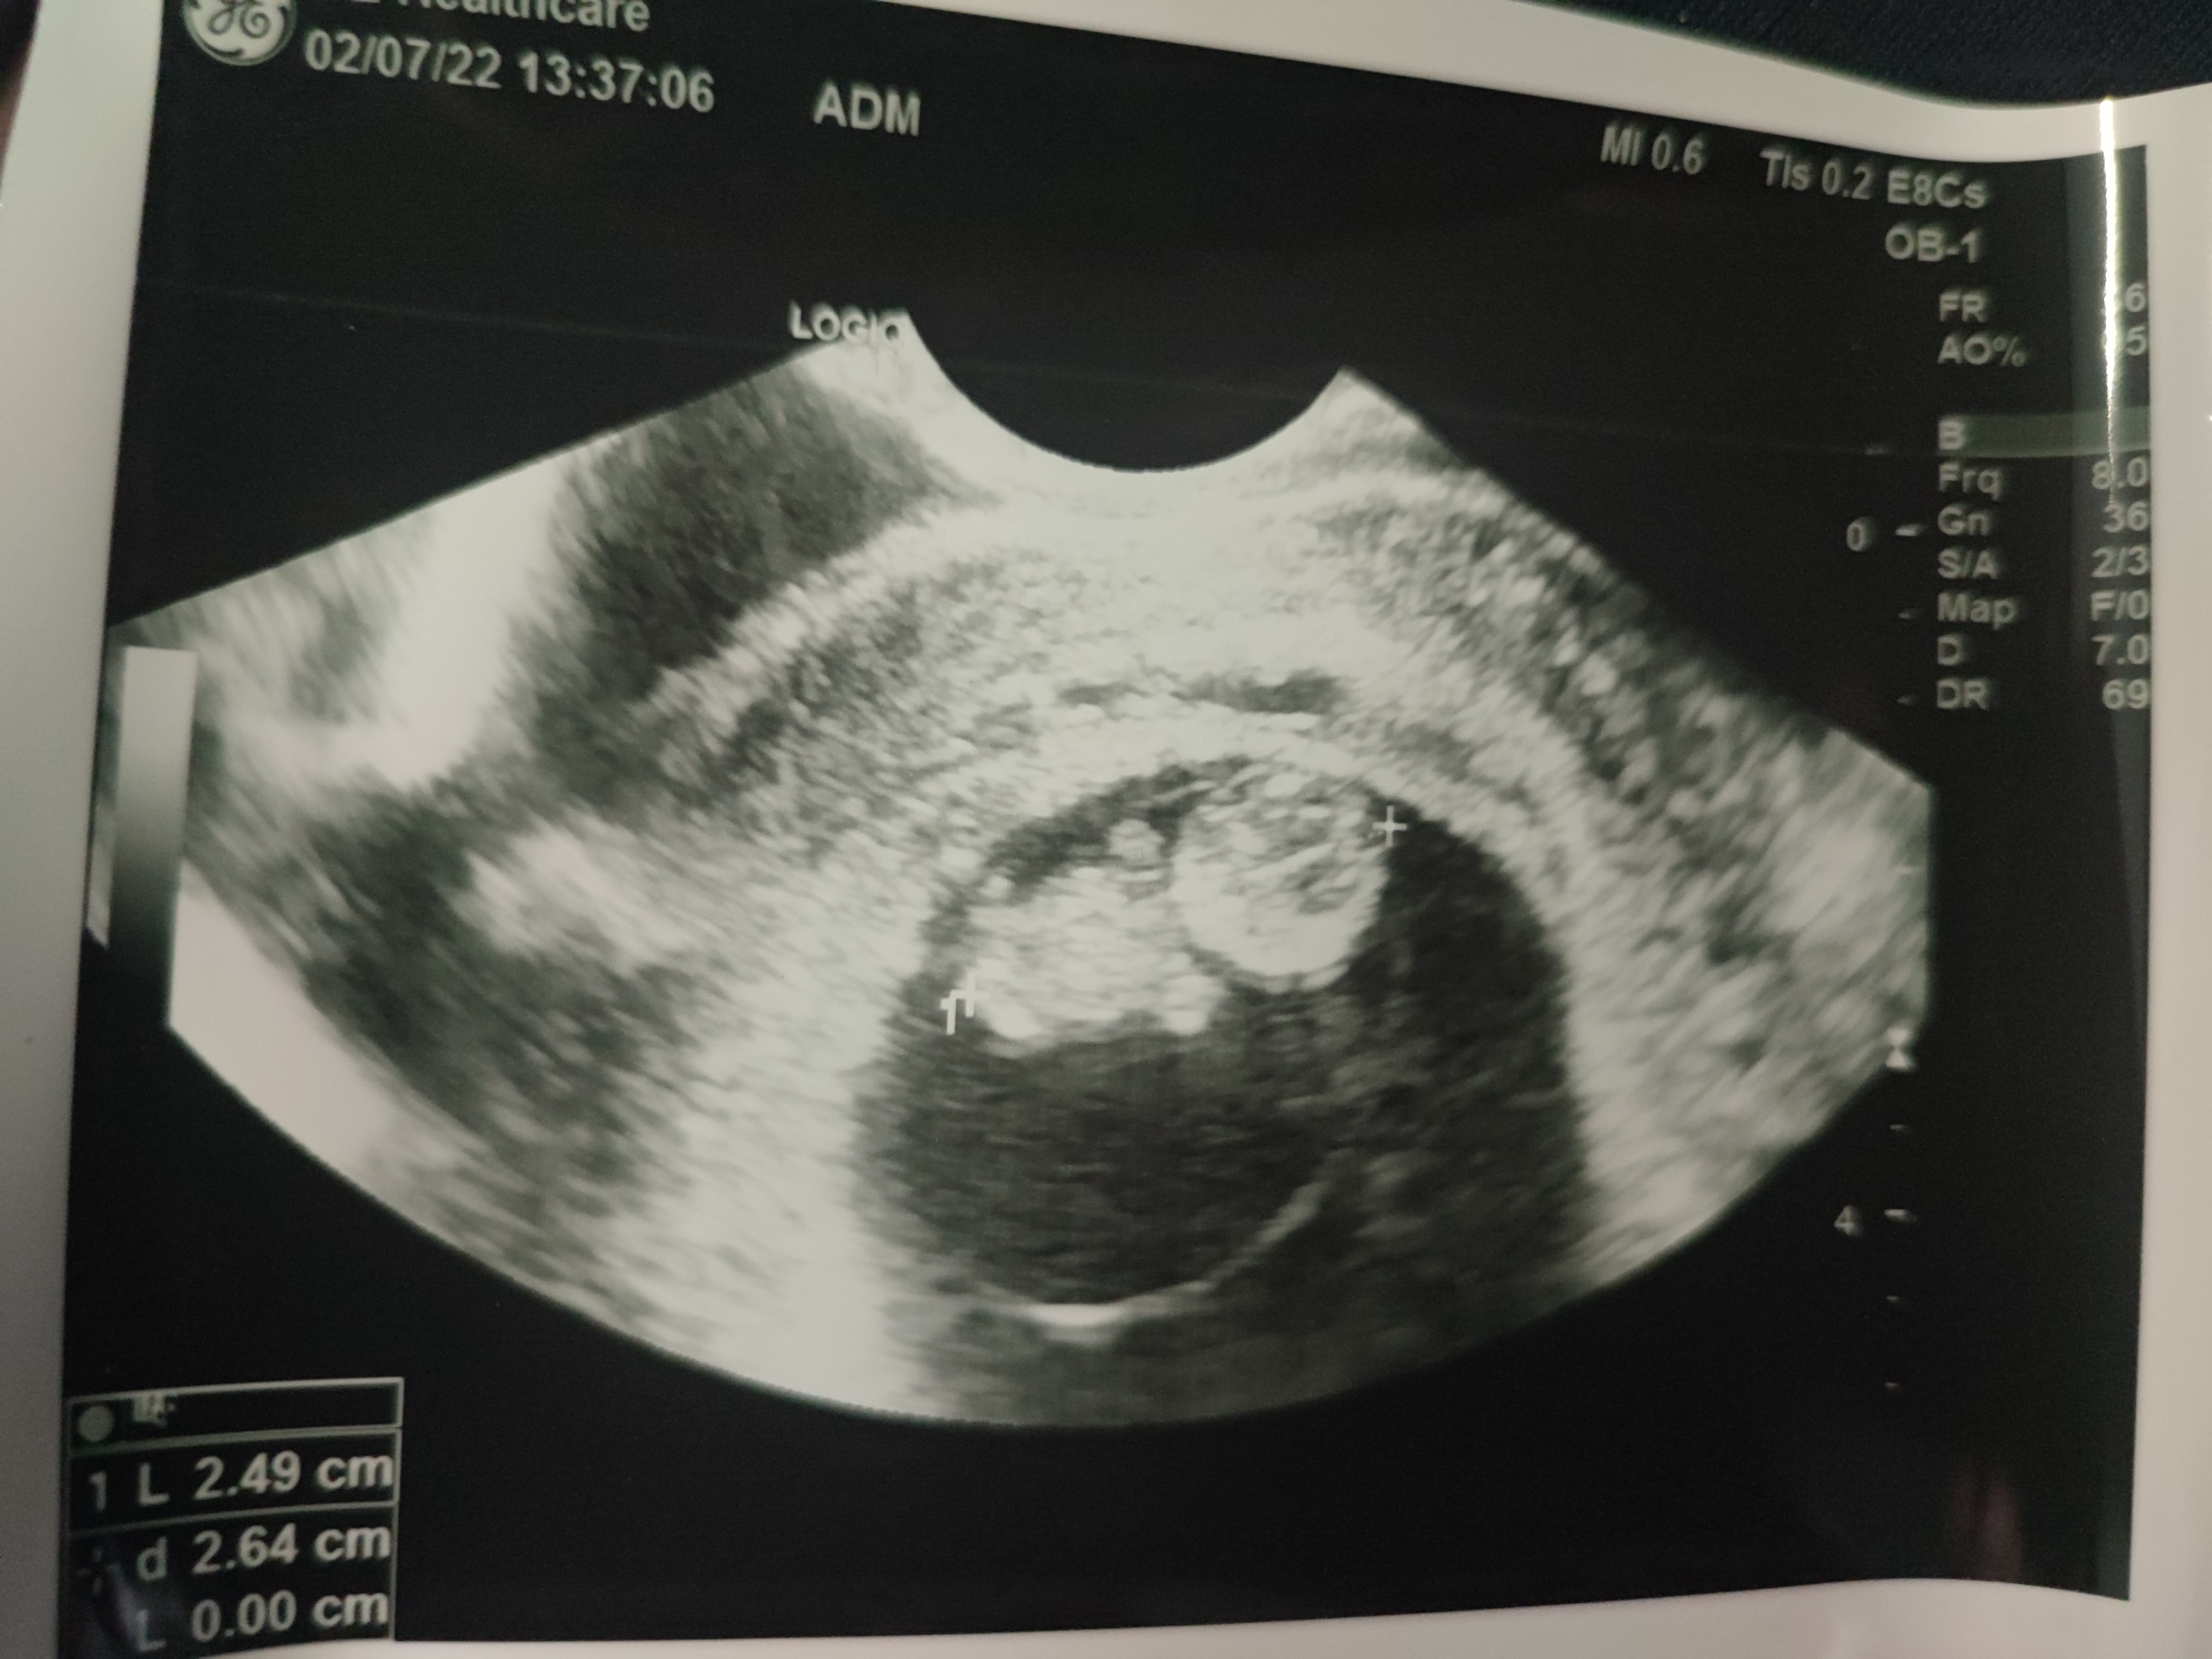

Byłam dziś u gina, z brzdącem ponoć ok..

Załączniki

• IMG_20220702_140410.jpg

IMG_20220702_140410.jpg

1,2 MB · Wyświetleń: 120